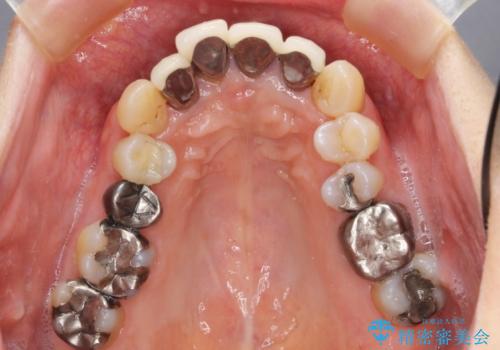

- 上顎前歯の黒ずみの改善、下顎前歯の十度なガタつき、矯正治療とセラミック治療を含む全体的な治療を希望され来院されました。

銀歯を高強度の仮歯に替えたのち、下顎前歯のみの部分矯正→全体的なマウスピース矯正治療(インビザライン)→最終的なセラミック治療と治療を進めます。

矯正治療と目立つ銀歯のやりかえを行ったことでかみあわせだけでなく、審美性・清掃性も改善し口腔内の環境を劇的に改善することができました。